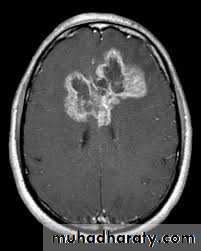

meningioma presented as isodense area or slightly hyper density area with surrounded crescent of hypo density ( csf cap ) post contrast injection the lesion enhance homogeneously with enhancing Dural tail .

20 % show calcification

hyperostosis & thickening of the near by bony part of the skull & diplioc space .

it may be associated with little or no peri focal edema .